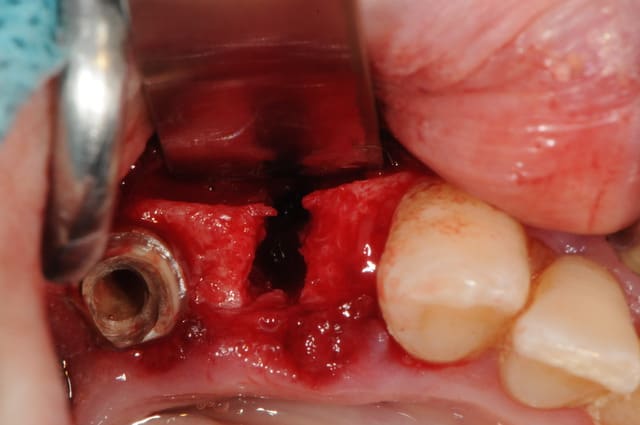

la preuve par 9...

3ième photo , c'est j+3 mois.